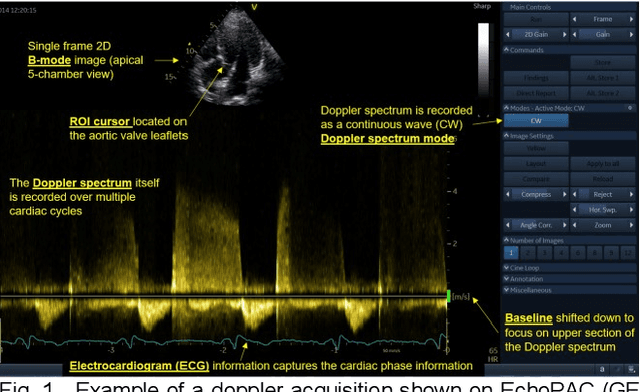

Abstract:Spectral Doppler measurements are an important part of the standard echocardiographic examination. These measurements give important insight into myocardial motion and blood flow providing clinicians with parameters for diagnostic decision making. Many of these measurements can currently be performed automatically with high accuracy, increasing the efficiency of the diagnostic pipeline. However, full automation is not yet available because the user must manually select which measurement should be performed on each image. In this work we develop a convolutional neural network (CNN) to automatically classify cardiac Doppler spectra into measurement classes. We show how the multi-modal information in each spectral Doppler recording can be combined using a meta parameter post-processing mapping scheme and heatmaps to encode coordinate locations. Additionally, we experiment with several state-of-the-art network architectures to examine the tradeoff between accuracy and memory usage for resource-constrained environments. Finally, we propose a confidence metric using the values in the last fully connected layer of the network. We analyze example images that fall outside of our proposed classes to show our confidence metric can prevent many misclassifications. Our algorithm achieves 96% accuracy on a test set drawn from a separate clinical site, indicating that the proposed method is suitable for clinical adoption and enabling a fully automatic pipeline from acquisition to Doppler spectrum measurements.